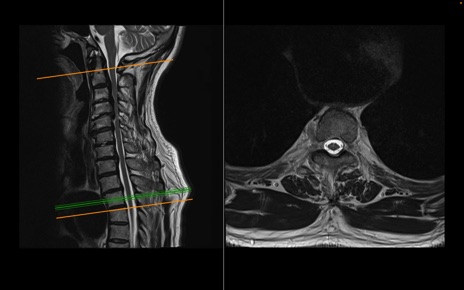

頚椎MRI

T2WI(横断像)

T2WI(矢状断像)